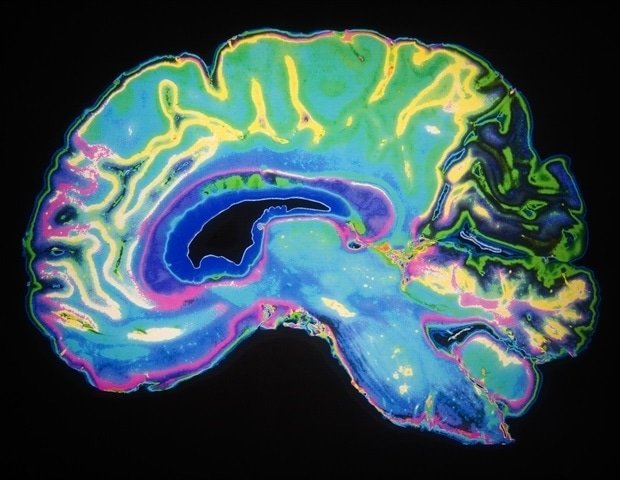

Your brain starts out as a single cell. When all is said and done, it will house an incredibly complex and powerful network of some 170 billion cells. How is it organized along the way? Cold Spring Harbor Laboratory neuroscientists have come up with a surprisingly simple answer that could have far-reaching implications for biology and artificial intelligence.